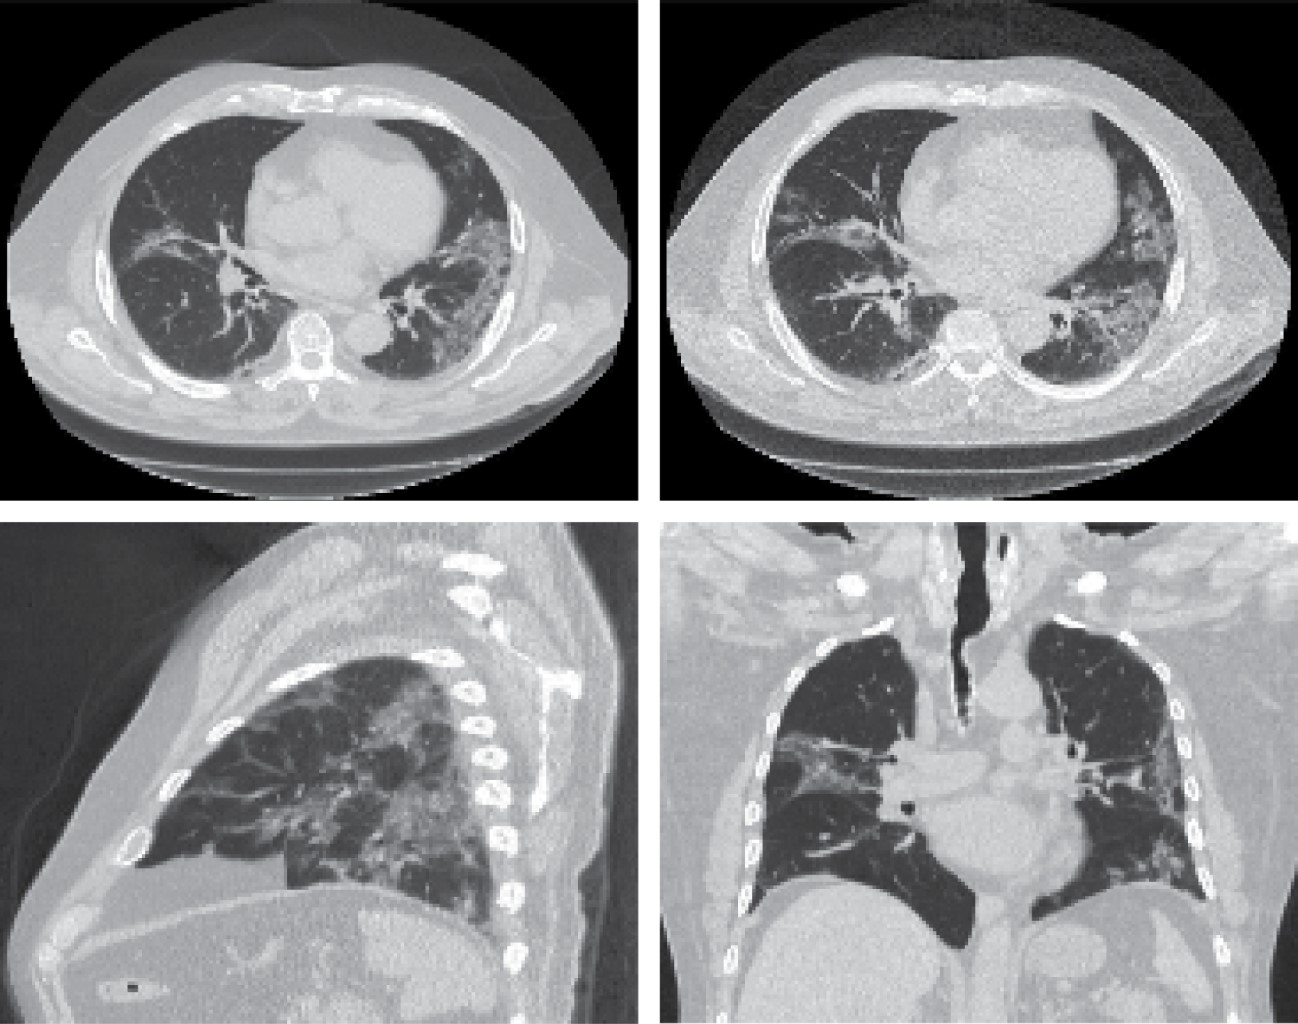

Los análisis de sangre revelaron: leucocitos 6.61 × 103, neutrófilos 5.05 × 103 (76.30%), linfocitos 0.92 × 103 (13.90%), hemoglobina 13.70 g/dL, hematocrito 39%, plaquetas 521 × 103, glucosa 105 mg/dL, BUN 43.6 mg/dL, urea 93.3 mg/dL, creatinina 4.74 mg/dL, TGP 52 UI/L, TGO 89 UI/L, DHL 784 UI/L, CK-MB ≥ 80.00 ng/mL, MYO ≥ 500 ng/mL, TNI 20.8 ng/mL, dímero D 4.09 μg/mL, ferretina 1,817.10 ng/mL, procalcitonina 0.48 (Tabla 1). Un electrocardiograma de 12 derivaciones mostró elevación del segmento ST en DII, DIII, aVF de 1.5 mm (Figura 1A). Los hallazgos en la radiografía de tórax se encontraron con múltiples infiltrados bilaterales diseminados (Figura 1B). Tomografía simple de tórax mostró parénquima pulmonar con patrón dominante en vidrio despulido de distribución periférica bilateral con predominio en hemitórax izquierdo, asociado a engrosamiento septal inter e intralobulillar conformando un "patrón en empedrado", dilatación vascular y bronquiectasias por tracción (Figura 2). Se realizó PCR para SARS-CoV-2 por los hallazgos radiológicos y tomográficos.

Figura 1